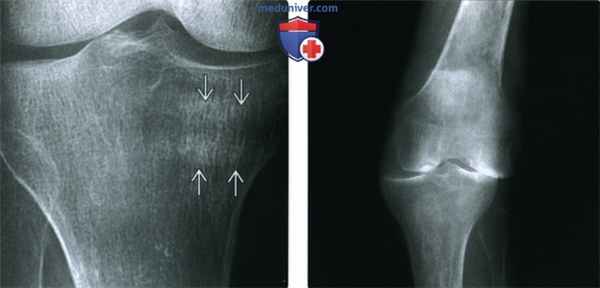

(Слева) Рентгенография в боковой проекции: признаки остеопении, наличия выпота в суставе и мягкотканного образования в заднем отделе без очевидной костной деструкции. Такая картина не является специфичной.

(Справа) МРТ, сагиттальная проекция, режим Т1 с подавлением сигнала от жира: визуализируется образование, представляющее собой скопление жидкости; МРТ в аксиальной проекции подтверждает, что это подколенная киста. Обратите внимание на утолщенную контрастированную стенку кисты, указывающую на наличие синовита, аналогично тому, который визуализируется в суставе. Определяются характерные для РА выраженное истончение хряща, небольшие эрозии и отек костного мозга.

(Слева) Рентгенография в ПЗ проекции: выраженная остеопения и умеренное сужение медиального отдела сустава у пациента с РА и впервые возникшей болью. Также обратите внимание на две склеротичные линии в структуре медиального мыщелка большеберцовой кости. Они являются диагностическими признаками патологического перелома.

(Справа) Рентгенография в ПЗ проекции является классическим методом исследования при РА. Визуализируются общее сужение суставного пространства и выраженная остеопения. Кроме того, имеется слабость связок, что определяется по медиальному смещению большеберцовой кости относительно бедренной кости. Также обратите внимание на характерную вальгусную деформацию коленного сустава.